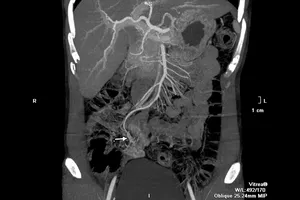

Nhập viện vì đau đầu, buồn nôn, không ngờ bị đột quỵ do xuất huyết não Y tế - Sức khỏe 18/02/2021 11:56